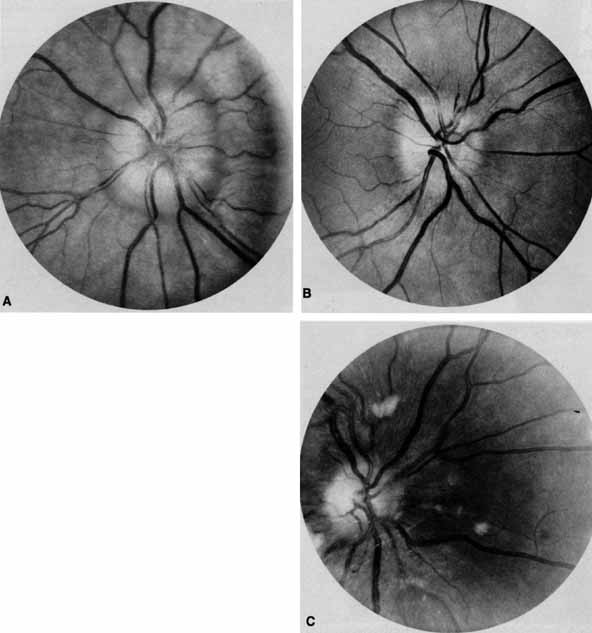

Ophthalmoscopy can be very helpful in orbital diagnosis. Optic disc edema may be caused either by papilledema (increased intracranial pressure) (Fig. 11A), papillitis (anterior optic neuritis) (Fig. 11B), or vasculitis (e.g., lupus erythematosus, sarcoidosis, Wegener's granulomatosis, and giant cell arteritis) (Fig. 11C).12 Papilledema (Fig. 11A) is usually present with near-normal visual function, although some patients may lose vision.9 In contrast, papillitis (Fig. 11B) characteristically leads to reduced visual function, commonly is associated with orbital pain, and is associated with inflammatory cells in the vitreous overlying the disc. Optic disc vasculitis (Fig. 11C) may be present with other findings of vasculitis, and commonly is associated with poor acuity and evidence of vascular occlusion (e.g., cotton-wool spots, hemorrhages). The differential diagnosis of the swollen, erythematous disc is discussed elsewhere in these volumes.

Fig. 11 A. Papilledema caused by pseudotumor cerebri. Visual acuity is 20/15 and the visual field is normal. B. Papillitis of anterior optic neuritis. Visual acuity is 20/400 with a relative afferent pupillary defect and a central scotoma. C. Vasculitis of optic disc caused by lupus erythematosus. Visual acuity is 20/200, there is a relative afferent pupillary defect, and a cecocentral scotoma. Note cotton-wool spots.